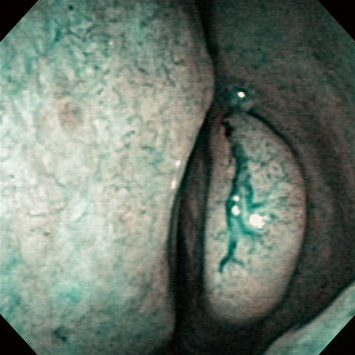

The Change Caused by 1:5000 Epinephrine Spraying

Before spraying

1 min. after spraying

3 min. after spraying

5 min. after spraying

Comment:

3 to 5 minutes after spraying 1:5000 epinephrine into the nasal cavity for a few seconds, constriction of the deeper vessels in the nasal mucosa was identified with NBI.

Images and comments by Dr. S. Takano <ENF-V2>